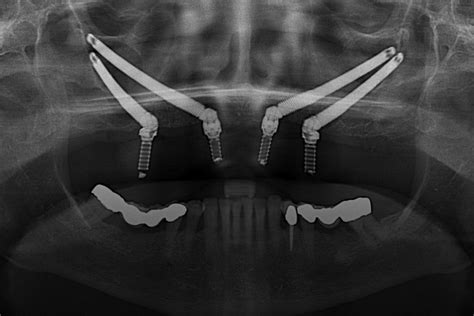

IOC Clínica Dental aterriza en Santa Cruz ofreciendo alternativas en tratamientos de implantología avanzada para esos pacientes para los que los implantes convencionales (endoóseos) ya no son una solución viable por la falta de hueso. Entre ellos, destacan los implantes cigomáticos, para pacientes con poco hueso maxilar superior.

También, el tratamiento de implantes subperiósticos, recomendados para casos en los que hay una pérdida grave de hueso en el maxilar o la mandíbula, el injerto óseo tampoco es viable, o requeriría de varias cirugías. Este tipo de implantes para maxilar superior e inferior evita cirugías de injertos óseos y múltiples sesiones, pudiendo incluso el paciente llevar dientes fijos en menos de 24 horas tras la intervención.